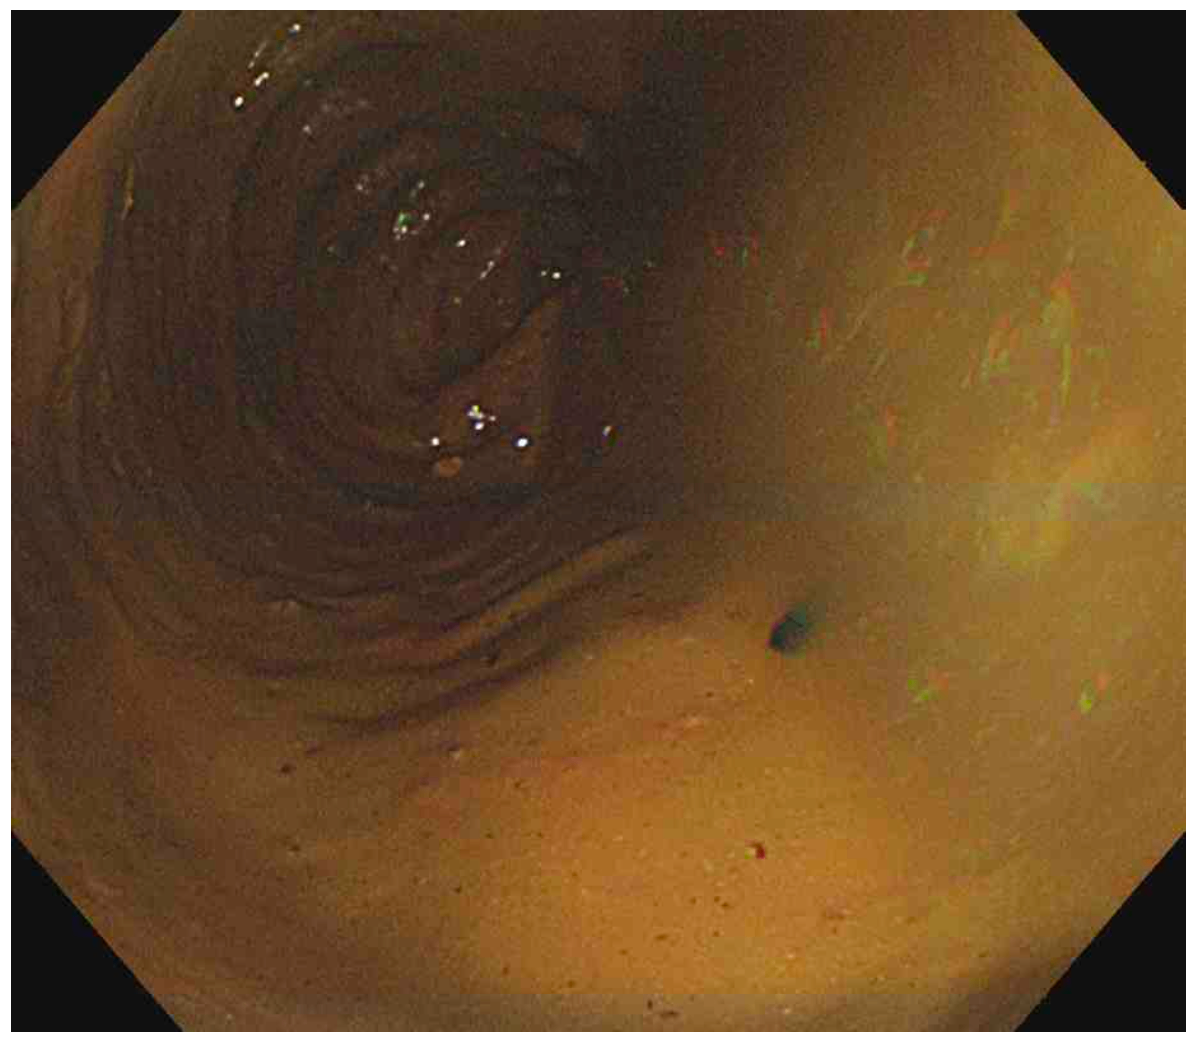

Sigmoidoscopy: No specific findings

• 장폐쇄를 유발한 원인을 확인하기 위해 추가적으로 시행한 sigmoidscopy상 기계적 폐쇄를 유발할만한 이상소견이 관찰되지 않는다.

• 만성적인 변비를 호소하는 환자의 복부 CT상 장폐쇄가 의심되지만, sigmoidoscopy상 특별한 이상소견이 없으므로 장거짓폐쇄(intestinal pseudo-obstruction)를 의심할 수 있다.

• 대장암: 구불창자내시경상 대장암을 의심할만한 병변이 확인되지 않으므로 대장암의 가능성은 낮다.

• 대변매복(fecal impaction): 변비가 장기화되어 직장에 대변이 돌처럼 굳어있는 상태를 의미한다. 구불창자내시경상 대변매복이 관찰되지 않으므로 가능성은 낮다.